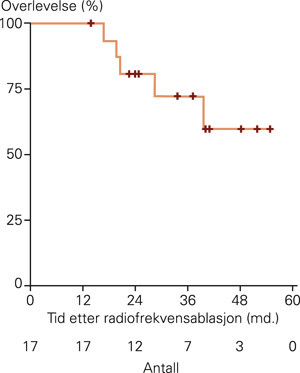

RF ablation was used to treat one liver metastasis in each patient, and was combined with liver resection in seven patients. The median follow-up time after RF ablation was 29 months ((14) – 55). One-year survival was 100 % and survival after both two and three years was 67 %. Follow-up examinations revealed local tumour progression at the RF-treated site in eight patients, intrahepatic recurrences not related to the RF-treated site in eight patients and extrahepatic recurrence in nine patients. Four patients with intrahepatic recurrence were re-treated with a curative intent.

Overlevelse

Median overlevelse var 29 måneder. Ettårs-, toårs- og treårsoverlevelse var henholdsvis 100 %, 67 % og 67 %. Fem pasienter døde i oppfølgingstiden, henholdsvis 17, 20, 21, 29 og 40 måneder etter radiofrekvensablasjon (fig 3). To av disse pasientene var behandlet med radiofrekvensablasjon alene, tre med kombinert radiofrekvensablasjon og reseksjon. De resterende 12 pasientene er i live med median oppfølging 36 måneder (spredning 14 – 55).

Ubehandlet har pasienter med kolorektale levermetastaser dårlig prognose, med median overlevelse 6 – 12 måneder (14, 15). I en prospektiv studie av 484 ubehandlede pasienter med kolorektale levermetastaser ble det funnet median treårsoverlevelse på 0,9 % (16). Det etablerte behandlingstilbudet for pasienter med ikke-resektable kolorektale levermetastaser er kjemoterapi med forventet median overlevelse 20 – 22 måneder og treårsoverlevelse 20 – 25 % (17, 18). I vår studie av pasienter behandlet med radiofrekvensablasjon var median overlevelse 29 måneder og treårsoverlevelse 67 %, med 12 av 17 pasienter fortsatt i live.